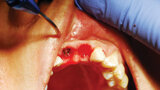

Fig. 5: When minimal keratinized gingiva is present, the diode laser is utilized to make an incision distal-mesially, and the tissue is spread conserving all of the attached gingiva present. (Photo provided by Dr. Gregori M. Kurtzman)